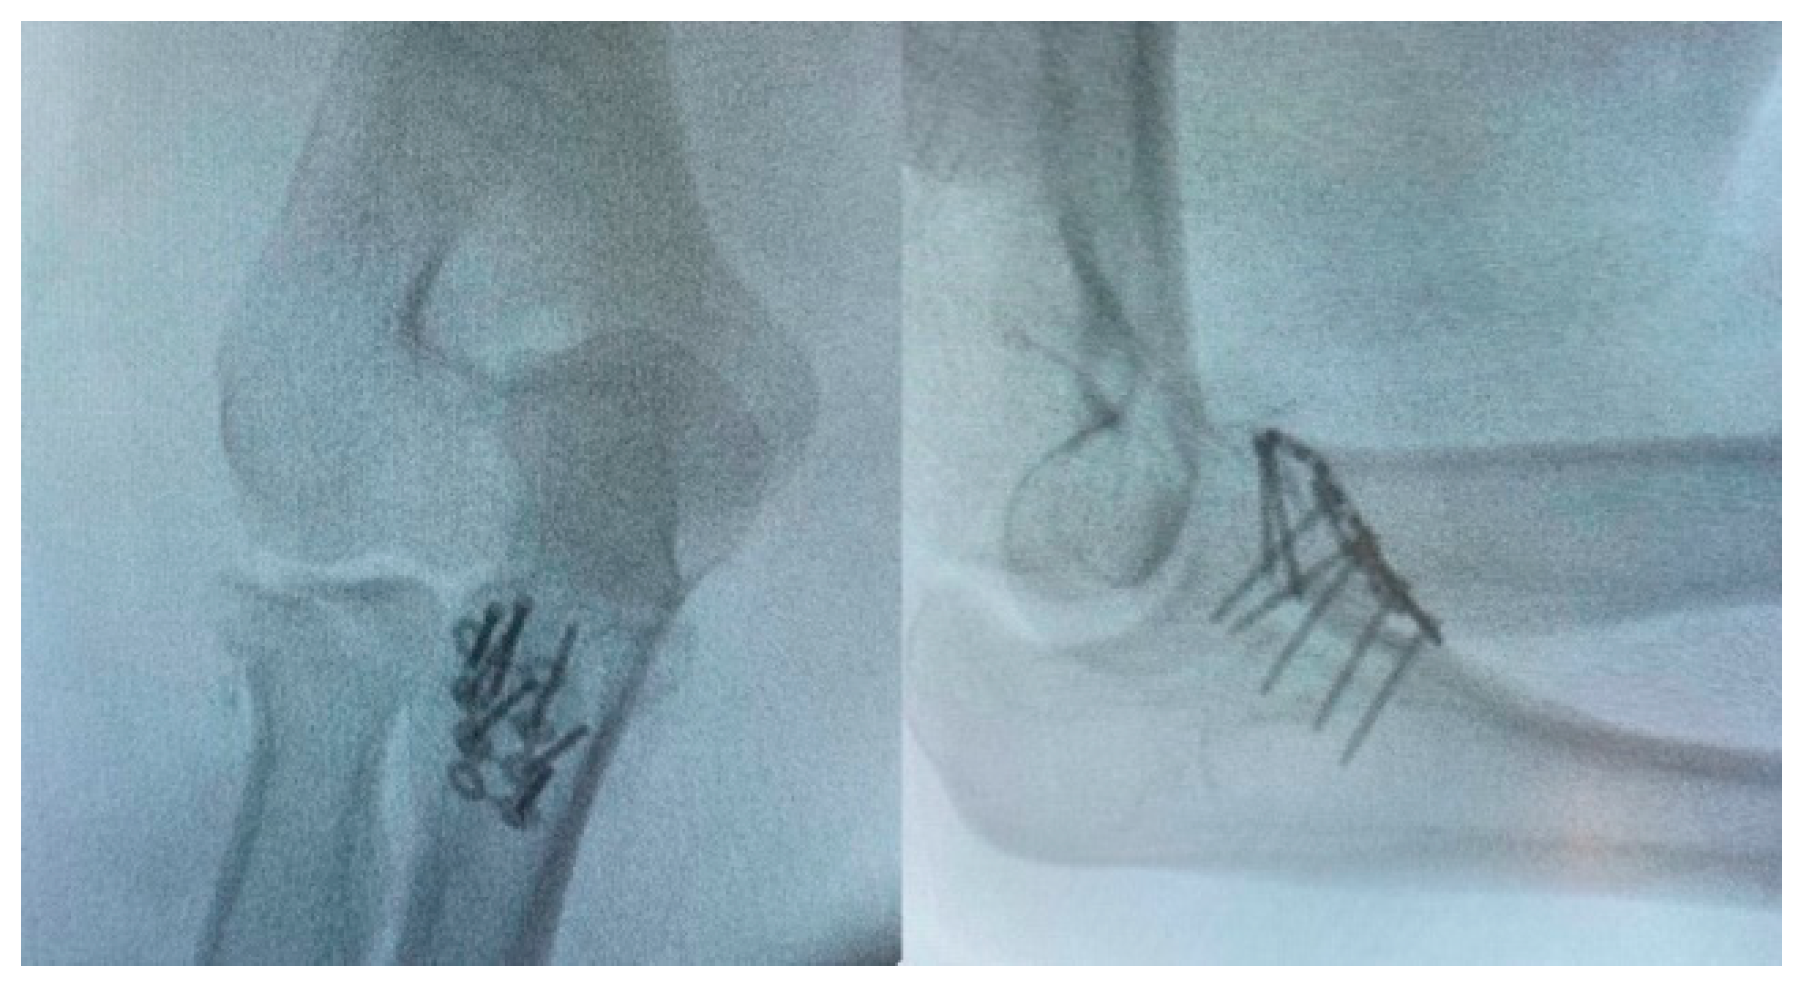

2.3. Fixation of Radial Head

2.4. Variant Proximal Ulnar Fractures and Ligaments Injuries